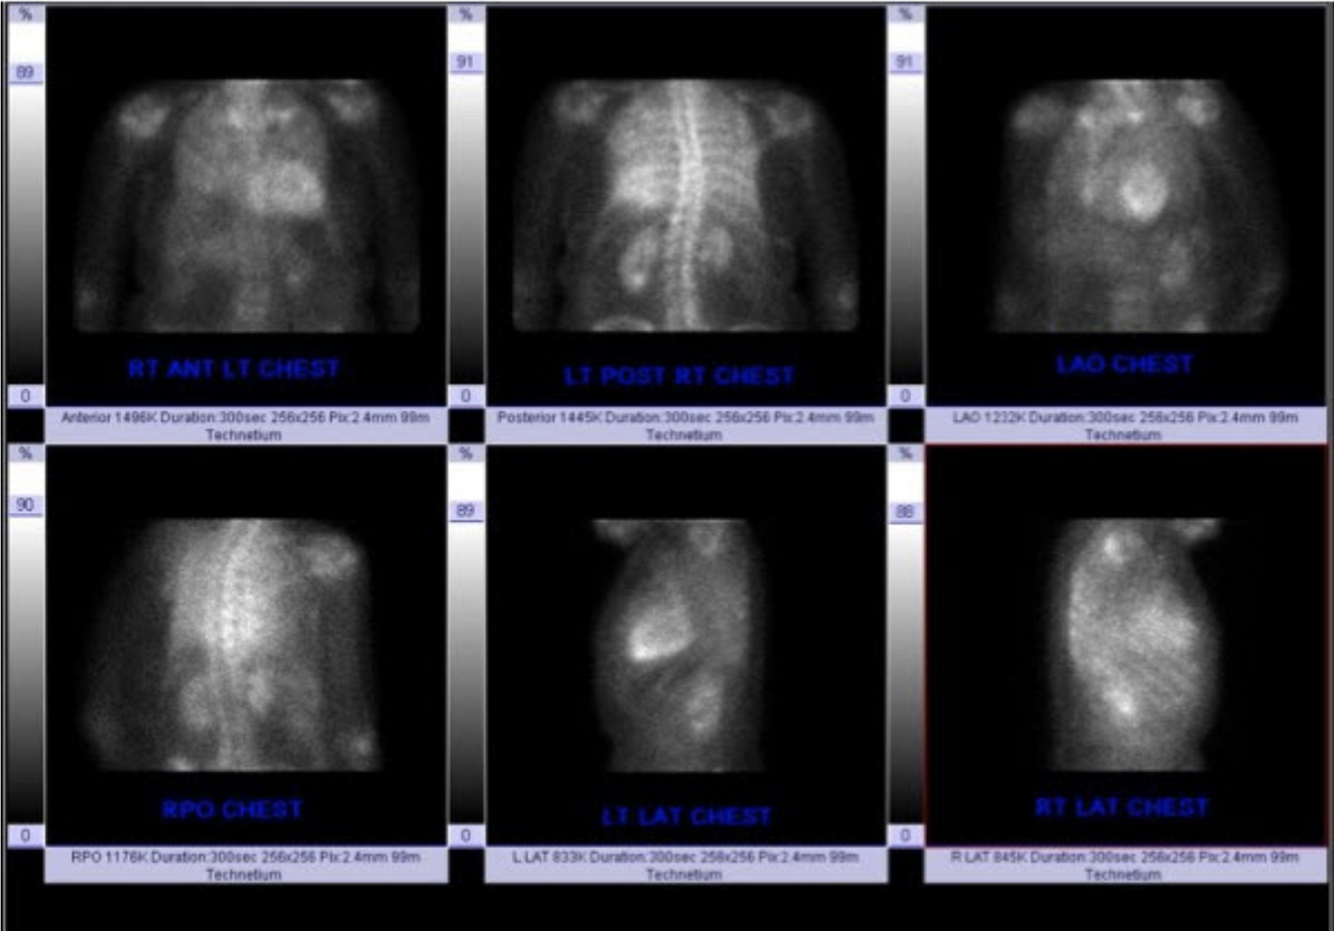

Desribe the findings and most likely cause of SOB:

COPD